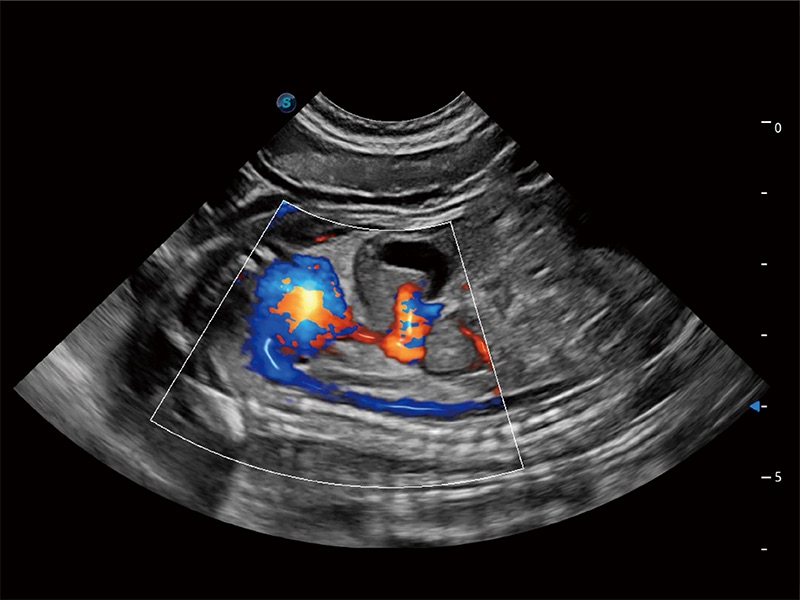

• Bright Flow 立体血流成像

在传统二维血流成像的基础上,呈现血流的立体感,具有动感的生命力之美。即便是微小的血管也能轻松应对,提高了血流的视觉敏感性。

(犬)二腔心血流